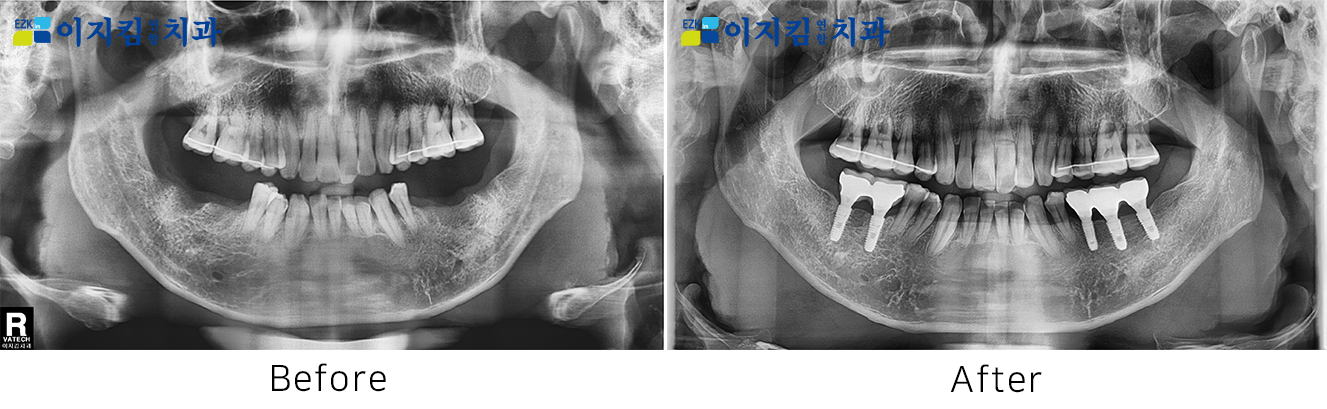

ÀÓÇöõÆ® Àü ¡¤ ÈÄ »çÁø